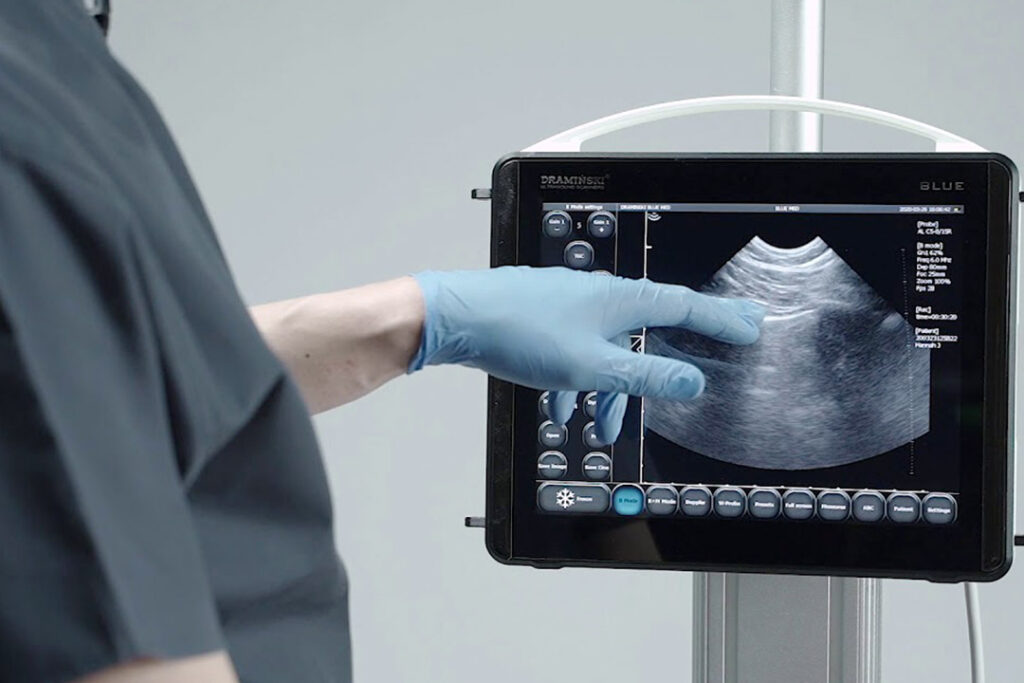

Ecografia del distretto toraco-addominale

- Direttori del Corso: A. Guarnera, R. Mistrulli

- Discipline: Medici chirurghi (tutte le discipline)

Ecografia polmonare nel paziente pediatrico

- Direttore del Corso: A. Testa

- Discipline: Pediatria, Pneumologia, Radiodiagnostica

Ecografia ostetrica

Direttore del Corso: L. Di Cagno,

G. Campobasso - Discipline: Ginecologia, Ostetricia

ECD venoso

- Direttore del Corso: A. Mele

- Discipline: Cardiologia, Medicina interna, Radiodiagnostica

ECD nefrologico

- Direttore del Corso: A. Zito

Discipline: Medicina d'Urgenza,

Medicina Interna,

Nefrologia, Radiodiagnostica

ECD tiroideo

- Direttore del Corso: A. Mele

- Discipline: Endocrinologia, Medicina interna, Radiodiagnostica